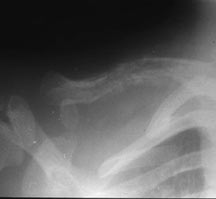

- May arise from any bone and any site within a bone (epiphyseal, metaphyseal, diaphyseal)

- Radiographically variable appearance: may appear benign (geographic) or malignant (permeative or moth eaten)

Sites:

- Flat Bones (most common—70%)

- Skull

- Pelvis

- Femur

- Humerus

Radiographic Presentation